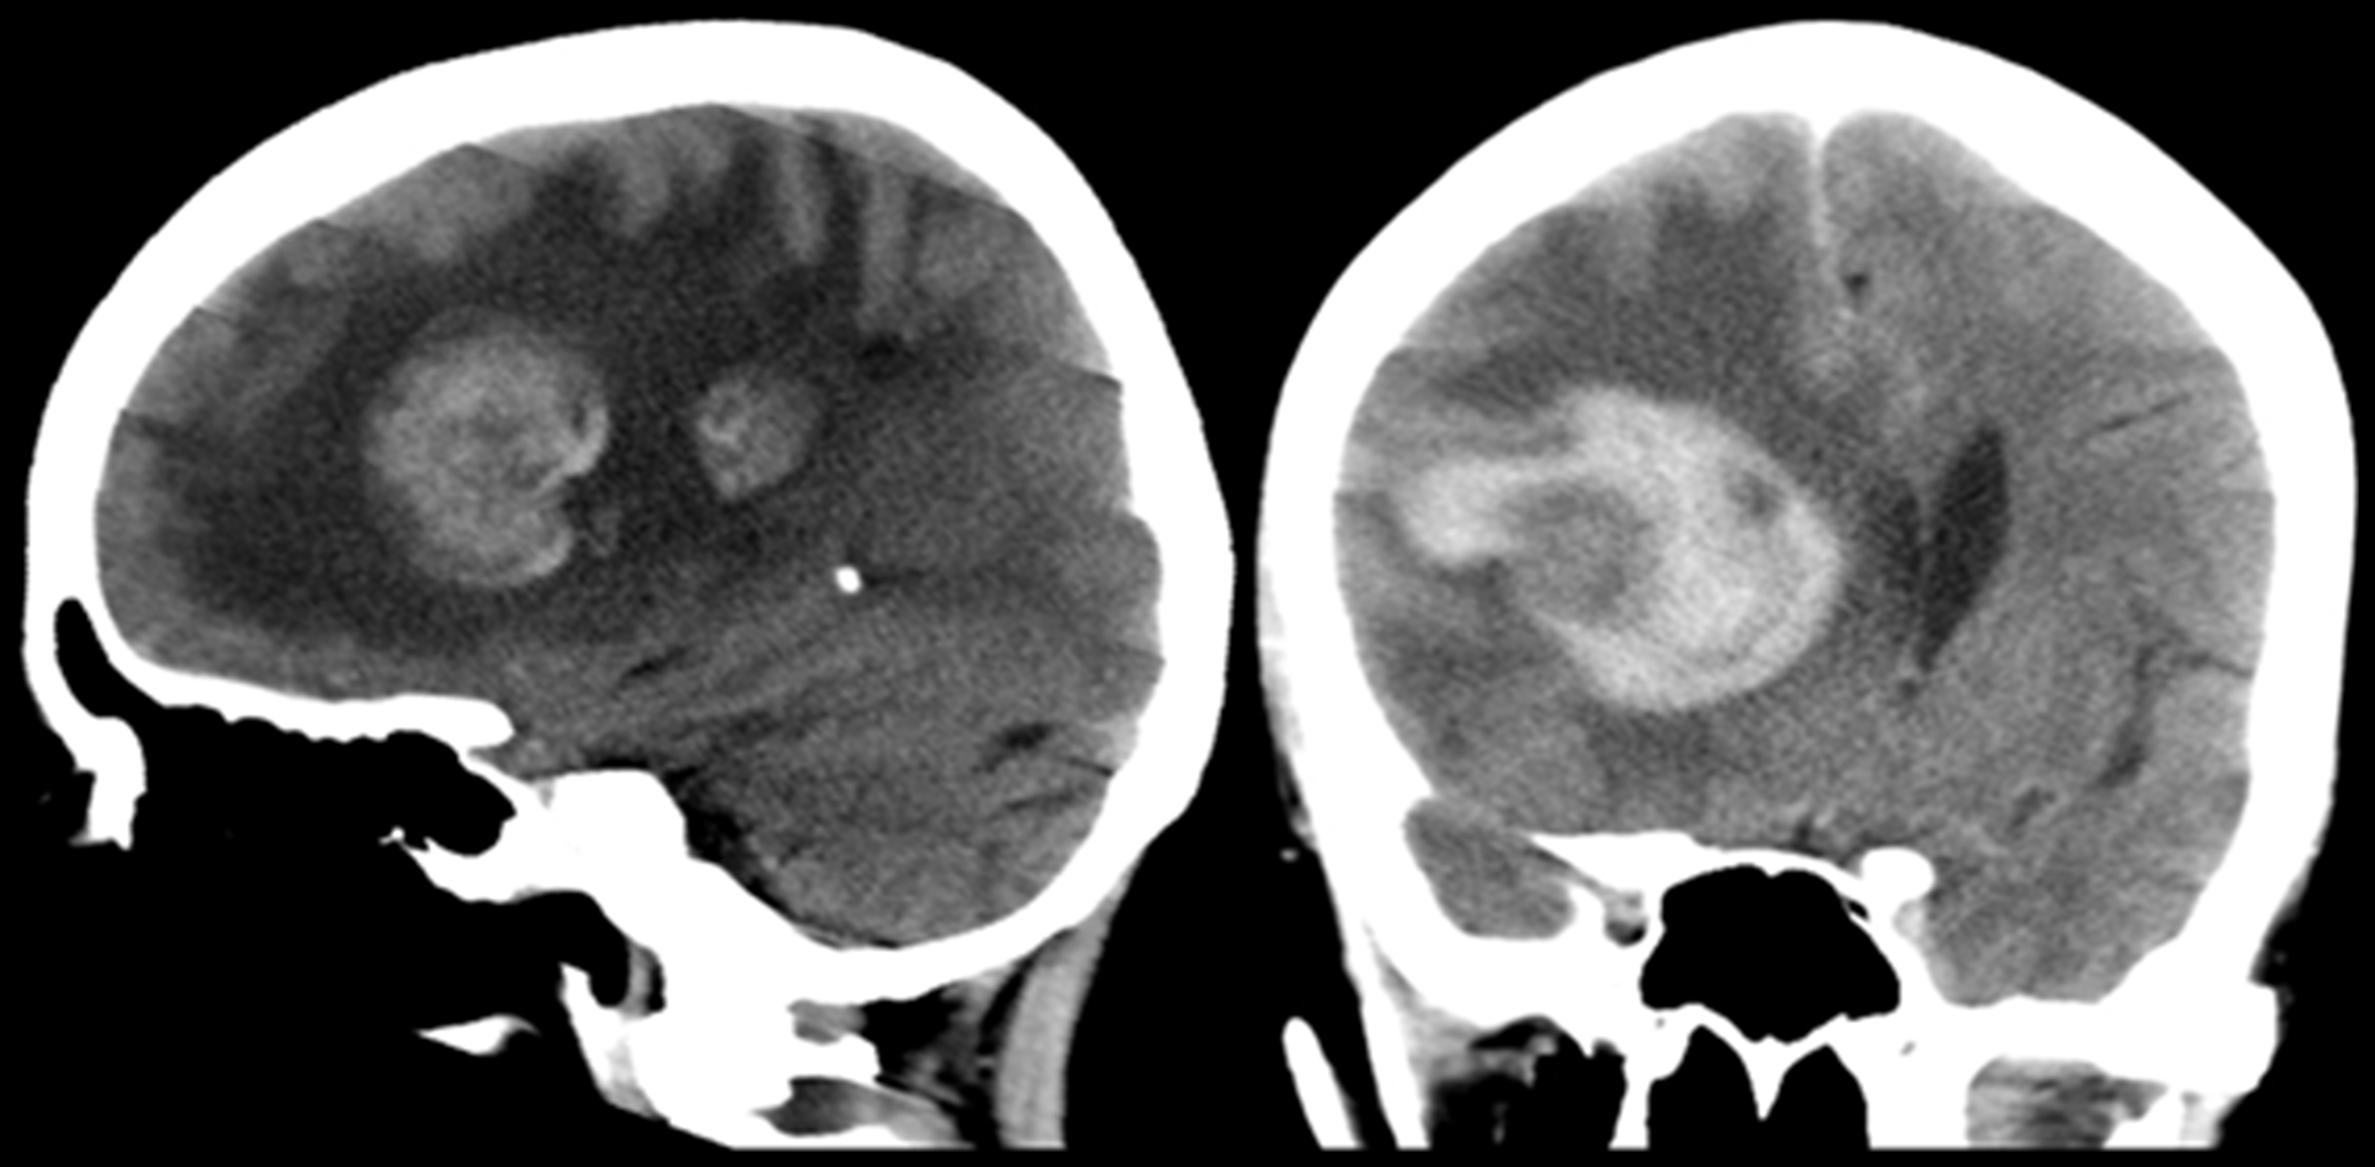

Se realiza TC de cráneo (Fig. 1), donde se constata la presencia de dos lesiones intra-axiales frontales derechas, con sectores espontáneamente hiperdensos en relación a sangrado. Ambas presentan realce en anillo grueso e irregular con el medio de contraste. En RM son de intensidad de señal heterogénea, hipointensas en T2/FLAIR (del inglés “fluid attenuated inversión recovery”), hiperintensas en T1, con realce periférico grueso, continuo e irregular con gadolinio. En secuencias eco de gradientes (GRE) se observan zonas de artificio de susceptibilidad magnética en relación a áreas de sangrado interno. En difusión-ADC (coeficiente de difusión aparente) se objetivan áreas periféricas de restricción y en el estudio de perfusión disminución del volumen sanguíneo cerebral (Fig. 2). Se completó estudio con TC de cuello, tórax, abdomen y pelvis, sin identificarse lesiones sugerentes de compromiso nodal, hepático o esplénico.

Con valores de CD4 de 37 cél/mm3 y carga viral de 283679 copias/ml, presenta peoría clínica, con depresión de conciencia, “score de coma de Glasgow” de 3, requiriendo intubación y asistencia respiratoria mecánica. En TC de control (Fig. 3), se constató aumento del tamaño lesional secundario a sangrado.

Figura 3

Control evolutivo

a) Corte sagital sin contraste.

b) Corte coronal con contraste iv. Frente a la peoría clínica se realizó tomografía de control. Se observa aumento de la lesión, secundario a sangrado intra-tumoral.